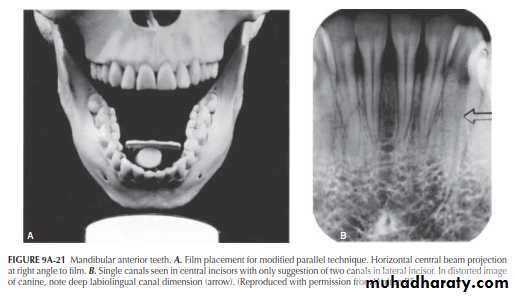

Mandibular Anterior Teeth

Aberrations in canal anatomy in the mandibular anterior teeth are not uncommon. Variance of the horizontal X-ray projections in this region will bring out the differences. Figure 9A-21A illustrates the standard X-ray projection bisecting the film held parallel to the arch. The incisor teeth appear to have single canals. However, a deep single canal is seen in the distorted canine image (Figure 9A-21B).By varying the film placement and projecting directly through the canine, as seen in Figure 9A-22A (about 30° variance for the incisors), separate canals appear in the incisors (Figure 9A-22B, arrow); the canals join at the apex. This would be expected. However, when viewing the tapered incisor roots seen in both horizontal projections, the roots are far too narrow to support two separate canals and foramina. Once again, the abrupt change in canal radiodensity in the premolars (arrow) indicates a canal bifurcation.